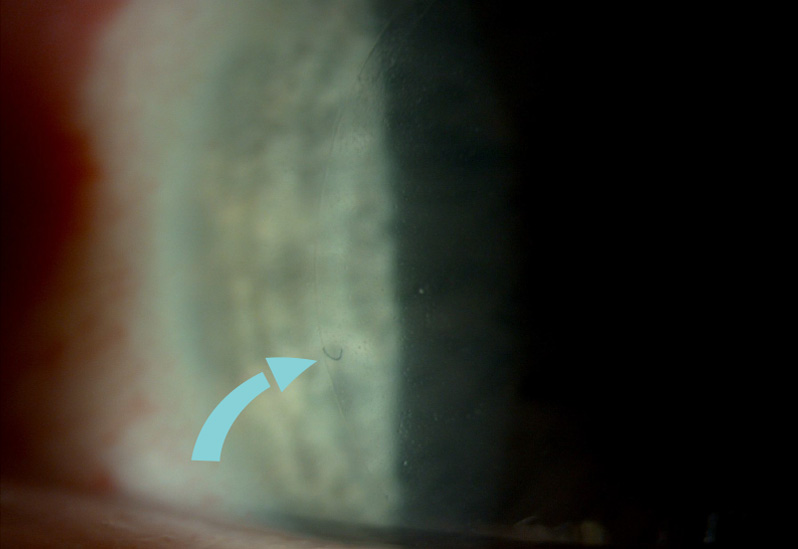

- Slit Lamp Exam